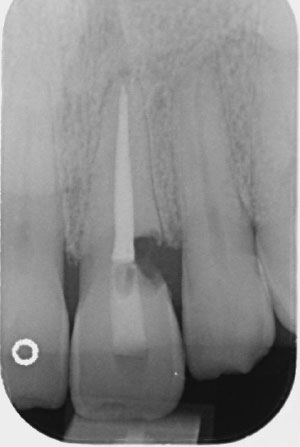

Immediate Implant UL1

Before

All stages of surgical and restorative work by Mr RS Khurana